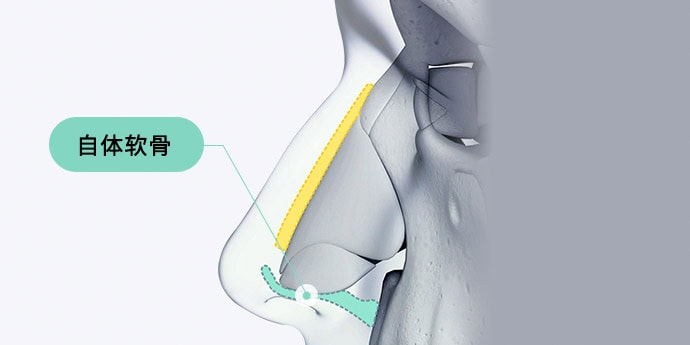

02. 自体组织

耳软骨

塑造自然鼻尖形态,

透光现象少的自体组织

鼻中隔软骨

位于鼻内部的软骨,是鼻整形中

最常用的自体组织材料

肋软骨

当耳软骨或鼻中隔软骨不足,或需要

更坚固的软骨时,常采用的植入材料

自体真皮

适用于鼻梁皮肤较薄或

软组织不足时的自体组织材料

通过使用自体组织,和谐地矫正

鼻梁与鼻尖,使其自然融合。